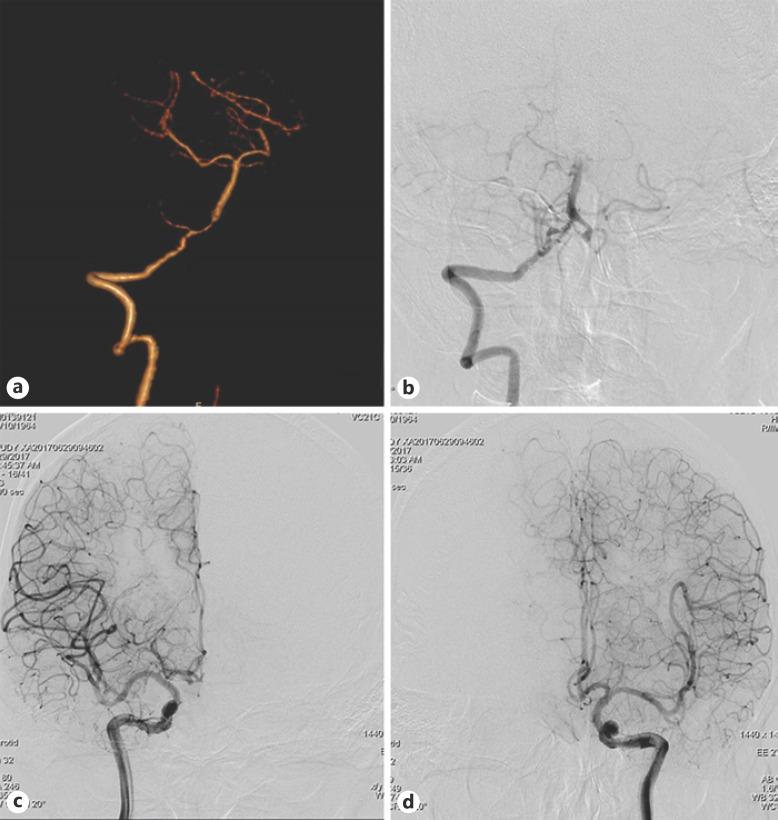

慢性症状性颅内椎基底动脉狭窄患者的脑血管危险因素与侧支代偿的关系。

Association between Cerebrovascular Risk Factors and Collateral Compensation in Chronic Symptomatic Intracranial Vertebrobasilar Stenosis.

The level of collateral compensation plays a pivotal role in chronic symptomatic intracranial vertebrobasilar stenosis (IVBS). This study aimed to evaluate the association between cerebrovascular risk factors and collateral compensation in chronic symptomatic IVBS.

METHODS

This single-center cross-sectional study retrospectively reviewed 238 patients with angiographically demonstrated IVBS and divided them into good collateral compensation (GCC) group (collateral grade: 3-4, n = 110) and poor collateral compensation (PCC) group (collateral grade: 0-2, n = 128). The demographic information, laboratory tests, and clinical data of the two groups were compared and assessed using univariate logistic regression. Multivariate logistic regression was employed to analyze the independent related factors of collateral compensation.

RESULTS

Hyperlipidemia, high-density lipoprotein (HDL), and fasting blood glucose (FBG) were significantly different between the two groups. Multivariate logistic regression analysis revealed that HDL (odds ratio [OR]: 1.134, 95% confidence interval [CI]: 1.081-1.190), FBG (OR: 0.945, 95% CI: 0.925-0.964), and hyperlipidemia (OR: 0.261, 95% CI: 0.129-0.527) were statistically independent related factors of collateral compensation. The receiver-operating characteristic (ROC) analysis provided cutoff values of 34 mg/dL and 135 mg/dL for HDL and FBG associated with GCC and PCC.

CONCLUSION

Higher HDL levels are associated with higher incidence of GCC, whereas higher FBG levels and hyperlipidemia are associated with higher incidence of PCC.